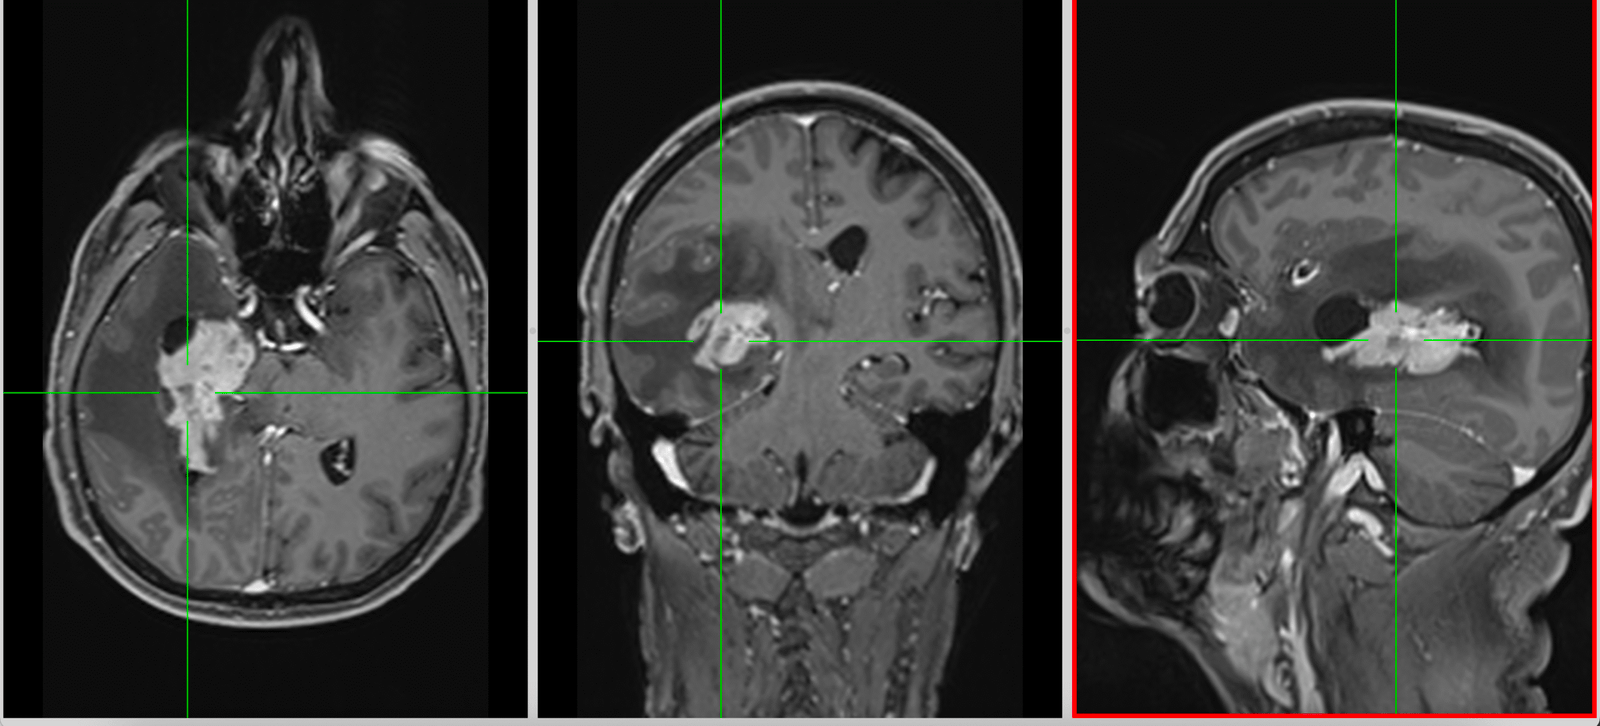

Chirurgia – rol central, dar nu curativ

Chirurgia reprezintă primul pas terapeutic și unul dintre cei mai importanți factori prognostici modificabili.

Conceptul actual este cel de rezecție maximală sigură, care implică:

- îndepărtarea cât mai extinsă a tumorii vizibile

- conservarea funcțiilor neurologice esențiale

Extensia rezecției este direct corelată cu supraviețuirea, însă beneficiul se pierde dacă este însoțit de deficit neurologic semnificativ.

Tehnologiile moderne au crescut semnificativ siguranța:

- fluorescența 5-ALA permite identificarea țesutului tumoral activ

- neuronavigația oferă orientare spațială precisă

- monitorizarea neurofiziologică protejează funcțiile motorii

- chirurgia awake permite cartografierea limbajului și a funcțiilor cognitive

În practică, fiecare intervenție este o negociere fină între radicalitate și funcție.

- Obligatoriu RMN cerebral cu contrast și protocol 3D pentru neuronavigație.

- Mijloace: microscop operator, neuronavigație, monitorizare neurofiziologică intraoperatorie (awake surgery), fluorescență 5-ALA.